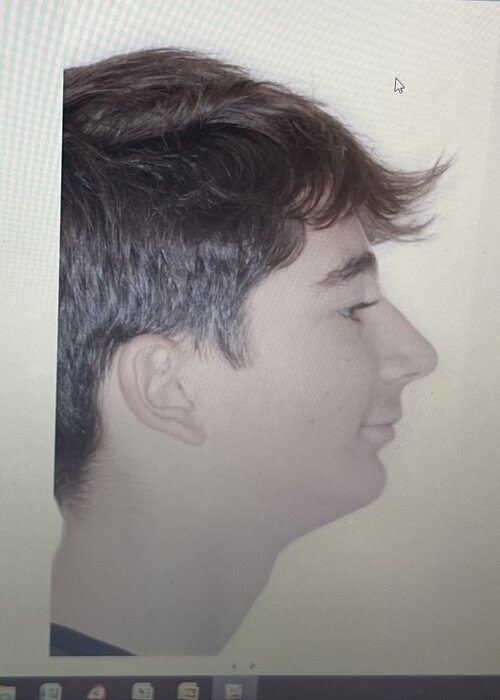

Important to note that my maxilla wasn’t downward grown until braces and headgear I am still 16 and upward thumb pressure is is not really doing anything much (I also had to fix my skeletal issue with my palate because my ortho only did tooth expansion instead of marpe/sarpe (aka breathing issues)